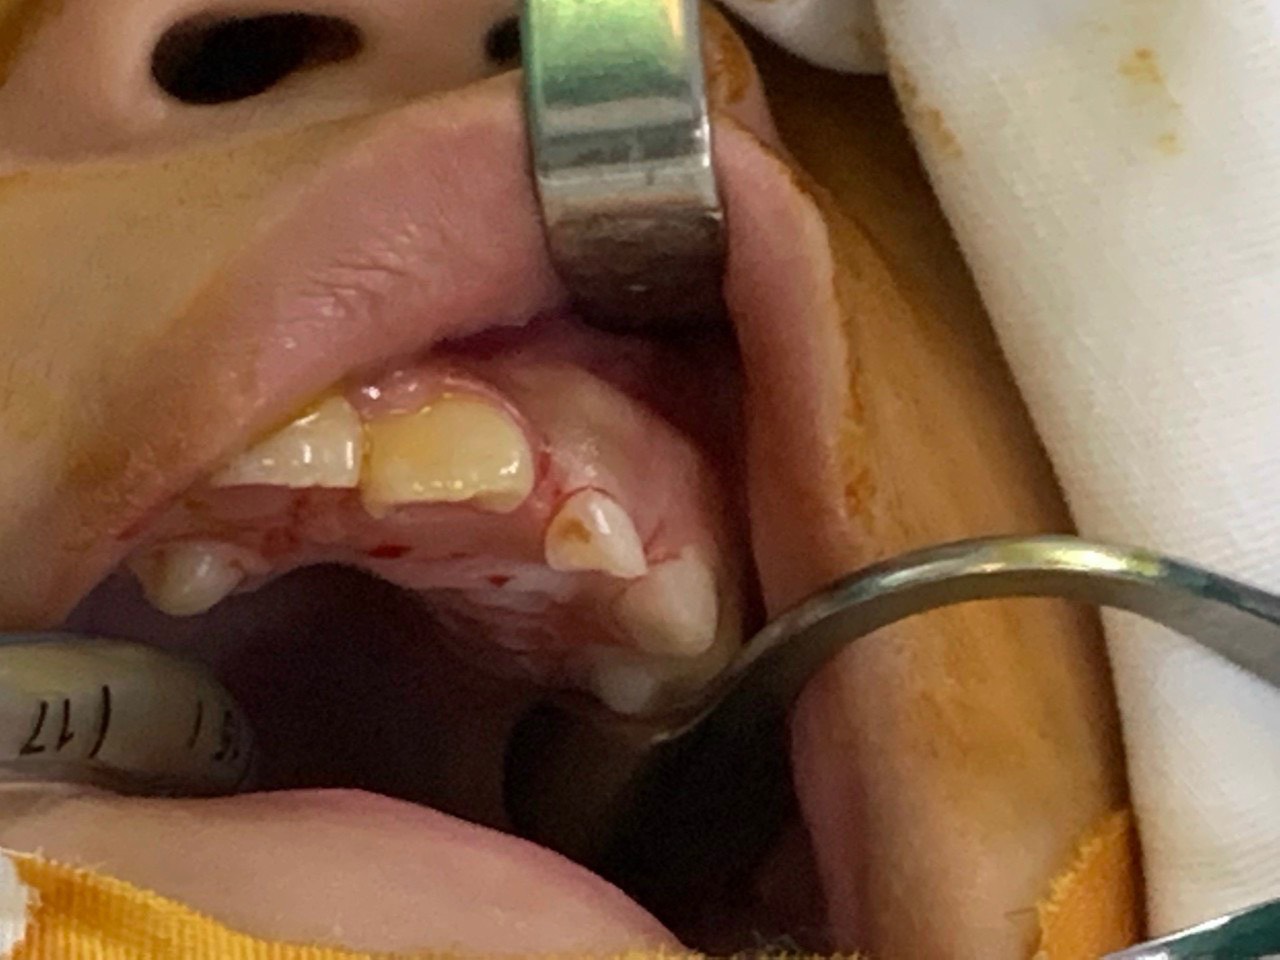

Trường hợp cháu N.T. T.D ( 9 tuổi, địa chỉ ở Minh Đức, Việt Yên) được bố mẹ đưa đến Bệnh viện Đa khoa tỉnh Bắc Giang khám do có răng thừa vùng hàm ếch. Sau khi được bác sĩ thăm khám và chụp X-quang xương hàm, phát hiện một khối u răng tương ứng với vùng răng số 22 và răng thừa vùng hàm ếch ngay sau răng số 11. Người bệnh được chẩn đoán: u răng vùng răng số 22 và được chỉ định phẫu thuật lấy u. Ca phẫu thuật kéo dài 60 phút, đã loại bỏ răng sữa số 2 bên trái, lấy răng thừa, loại bỏ khối u răng. Sau phẫu thuật bệnh nhân ổn định, vết mổ tốt, kiểm tra chụp X-Quang sau phẫu thuật không còn hình ảnh u răng.